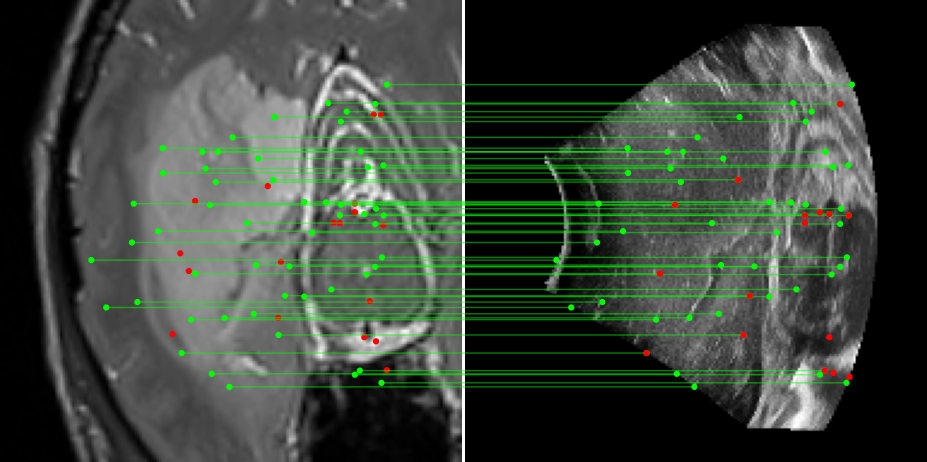

Figure 3: Examples of matching on three cases, one per column (MR on left and US on right). From top to bottom: SIFT+Cosine, MIND+Cosine, SP+Cosine, SP+LG, Ours+LG, Ours+Cosine. Correct matches recovered by each method are shown in green lines and mismatched are shown with a red dot.

To evaluate the performance of our model against existing image methods, we compared it to three approaches: SIFT [16], which remains the standard for keypoints matching, SuperPoint (SP) [3] built using a self-supervised learning approach and MIND [10], a modality-invariant descriptor for medical imaging, that although not designed for 1-to-1 keypoint matching, is extensively used for multimodal medical image registration through grid regularizing. We use SIFT and SP as keypoints detectors and descriptors, while we combine MIND with SP keypoints since it only provides a descriptor. We match these descriptors using both Cosine similarity and the deep neural network LightGlue (LG) [15] when possible (SP and Ours). Results reported in Table 2 and shown in Fig. 3 show that our approach outperforms these methods in terms of matching score, precision, and number of matched points. We only report results on three cases for readability reasons. Associating our descriptor with Cosine and LG reached similar performance depending on the metric.